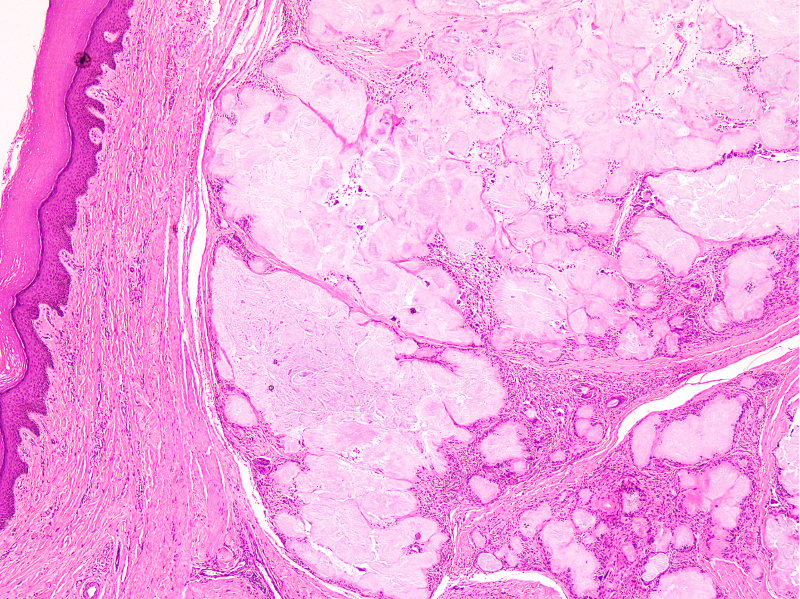

Microscopic (histologic) description

- Gout tophus:

- Nodular aggregates / granuloma-like appearance consisting of acellular, amorphous, pale eosinophilic material surrounded by palisading arrangement of histiocytes and multinucleated giant cells (Dermatol Online J 2015;21:13030)

- Feathery appearance in some deposits due to empty needle shaped spaces (Skeletal Radiol 2020;49:1325)

- Presence of monosodium urate crystals (MSU) is diagnostic

- Needle-like crystals that measure 5 - 25 micrometers in length

- Brightly anisotropic under polarized light

- Negative birefringence when examined with an interference plate in the light path (Otol Neurotol 2009;30:127)

- Crystals appear yellowish when aligned parallel to the plate axis

- Bluish appearance when alignment is across the direction of polarization

- Skin changes:

- Skin changes include calcification, fat necrosis, granulomatous dermatitis and hemosiderin deposition

- Thin epidermis, parakeratosis and hyperkeratosis

- Increased melanin pigment and pigment laden melanophages in superficial dermis

- Dermis shows dilated blood vessels, endothelial cell swelling and perivascular small mononuclear cell infiltrate (BMC Musculoskelet Disord 2019;20:140)